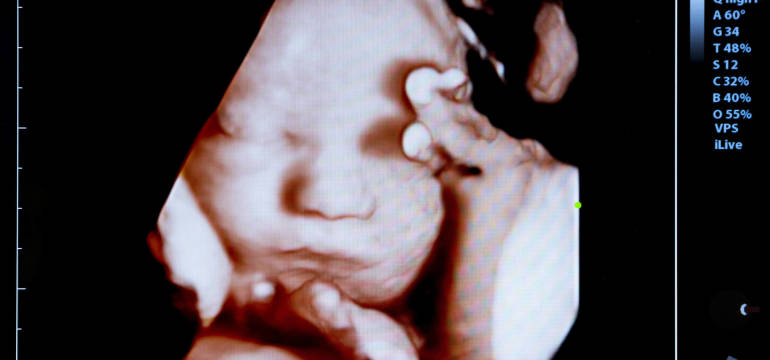

Ultrasonografia to wykorzystywana od wielu lat bezinwazyjna metoda wykorzystywana m.in. przy kontrolowaniu rozwoju płodu. Najnowocześniejszym rozwiązaniem technologicznym jest trójwymiarowe USG 4D, które oprócz obrazowania przestrzennego, ukazuje dodatkowo dziecko i jego aktywność ruchową w czasie rzeczywistym. W jakim celu można wykorzystać tę metodę badania płodu?

USG 4D swoją charakterystyką przypomina film w wysokiej jakości, na którym rejestrowane są ruchy płodu i jego dokładny obraz. Takie rozwiązanie daje zatem możliwość nie tylko obserwacji dziecka, ale przede wszystkim dokonania rzetelnej oceny jego rozwoju. Dzięki nowoczesnej technologii USG 4D możliwe jest o wiele łatwiejsze i przede wszystkim szybsze wykrycie wszelkich nieprawidłowości zdrowotnych, w tym nawet wad wrodzonych. Obrazowanie przestrzenne w postaci trójwymiarowego USG jest również świetną metodą dla rodziców chcących poznać płeć swojego dziecka.

Mogą oni nie tylko zbadać płód pod tym kątem, ale także zobaczyć swoją nienarodzoną jeszcze pociechę. Wysoka dokładność badania daje możliwość zarejestrowania nawet tak niewielkich szczegółów, jak mimika dziecka. USG 4D wykonują jednak wyłącznie sprawdzone, dobrze przygotowane gabinety ginekologiczne, takie jak np. USG Centrum. W tym miejscu można przeprowadzić właśnie taką kontrolę rozwoju płodu, co daje szereg informacji dzięki dostępnym rodzajom renderingu.

Połączenie zapisów USG 3D i 4D daje możliwość stworzenia obrazu przestrzennego nienarodzonego dziecka. Jest to rendering, który z kolei może być wykonany na kilka sposobów, dając tym samym różnego typu informacje o płodzie. Jednym z trybów renderingu jest tzw. wygładzenie powierzchni. W ten sposób odwzorowuje się struktury otoczone płynami. Dłonie, stopy i inne struktury kostne są natomiast widoczne w wyniku renderingu w trybie maksymalnym.